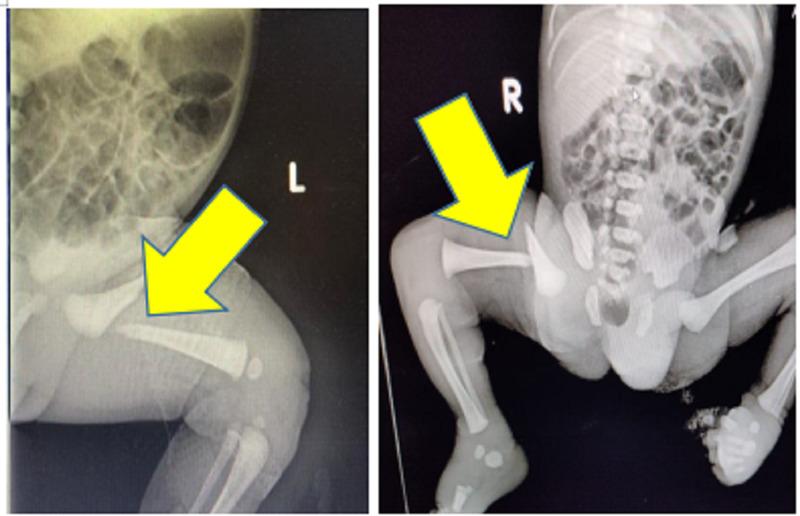

新生儿股骨干骨折:两例报告

Femur Shaft Fracture in Newborns: A Report of Two Cases.

Birth injuries caused by trauma during the childbirth process are very rare. They are a cause of significant neonatal morbidity despite improved obstetric and perinatal care, particularly in developing countries. Our current research, consisting of two newborns with a femur fracture, aims to shed light on their treatment strategy.

摘要